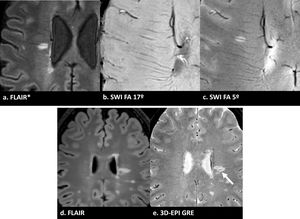

(a) Imagen FLAIR* que muestra una lesión de sustancia blanca con un signo de la vena central claramente visible (flecha). (b) SWI procesada estándar (flip angle 17°): la lesión aparece sutilmente hipointensa debido a la potenciación T1, dificultando su distinción de la sustancia blanca circundante y oscureciendo la identificación del CVS. (c) SWI procesada optimizada (flip angle 5°): la misma lesión ahora aparece hiperintensa debido al aumento de la potenciación T2*, con la vena central claramente visible. Esto ilustra por qué se recomienda la optimización del flip angle bajo o la fusión FLAIR* para una evaluación fiable del CVS. (d) otra imagen FLAIR de un paciente diferente, y (e) imágenes 3D-EPI GRE alineadas del mismo paciente que muestran claramente el CVS (flecha).

Consideraciones prácticas. La secuencia óptima para la visualización de CVS es la imagen ecoplanar de eco gradiente 3D (3D-EPI GRE). Con algunos proveedores, esta secuencia se adquiere de forma segmentada, lo que reduce el tiempo de adquisición. Además, en algunos sistemas, también permite la reconstrucción de imágenes de fase, lo que permite la detección simultánea de PRL. SWI La imagen por susceptibilidad magnética (SWI por sus siglas en inglés) es una alternativa a las imágenes 3D-EPI, sin embargo, puede requerir una optimización adecuada de secuencias. Las secuencias SWI estándar pueden tener una ponderación T1 excesiva que hace que las lesiones sean iso- o hipointensas, ocultando la vena central; Se recomienda un flip angle más bajo (aproximadamente 5°)8. FLAIR*,FLAIR (fluid attenuated inversion recovery) generado mediante la multiplicación voxel de imágenes FLAIR registradas y 3D-EPI, representa un enfoque óptimo ya que muestra simultáneamente lesiones hiperintensas y venas hipointensas26. La administración de gadolinio durante o inmediatamente antes de la adquisición sensible a la susceptibilidad mejora la detección de CVS, especialmente a 1,5T8. Además, dependiendo de las características de ponderación, la SWI poscontraste demuestra un efecto de «brillo en T1» que puede mejorar la detección de lesiones captantes de gadolinio en comparación con la imagen estándar potenciada solo en T127. La prevalencia del CVS varía según la ubicación, siendo más alta en lesiones periventriculares (hasta un 94%) y de sustancia blanca profunda, con datos limitados para otras regiones6. El impacto de la optimización de secuencias en la detección de CVS se ilustra en la figura 2.